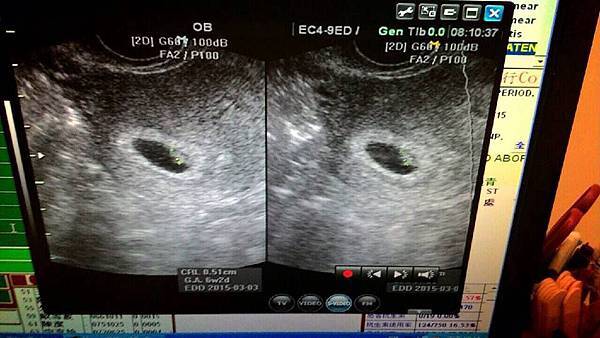

7/10(四) 6W2D 預產期2015.3.3 修正

跟小B仔二次見面 看到及聽到心跳